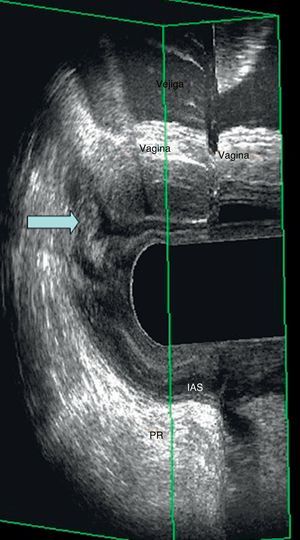

Enterocele por EEAD: visión de un asa intestinal entre la vagina y el recto durante el esfuerzo defecatorio, parecida a la imagen de una «mitocondria». Puede apreciarse tanto en la ecografía vaginal como en la rectal (fig. 3).

| 4.ª etapaa | Reposo 35 s. Esfuerzo defecatorio máximo durante 20 s. Reposo 15 s | Herniación de las paredes del recto o presencia de asas interpuestas entre la vagina y el recto | Grado de rectocele, grado III de enterocele/sigmoidocele e intususcepción rectal |